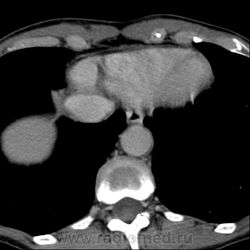

Обнаружилось небольшое образование низкой плотности, с достаточно ровными, четкими контурами парааортально справа около ножки диафрагмы на уровне тела L1 позвонка.

При нативе плотность 6HU, паренхиматозная - 18-20HU, экскреторная (15 минут) - 60-65HU.

Выкладываю по очереди срезы на одинаковых уровнях, сначала паренхиматозная, потом отсроченная фазы.

вот на этой картинке никто ничего подозрительного не заметил???

или я придираюсь или там что-то под правой почкой есть!!! сканограм побольше бы?!!!! можно еще немного кадров корон в венозную фазу выложить????